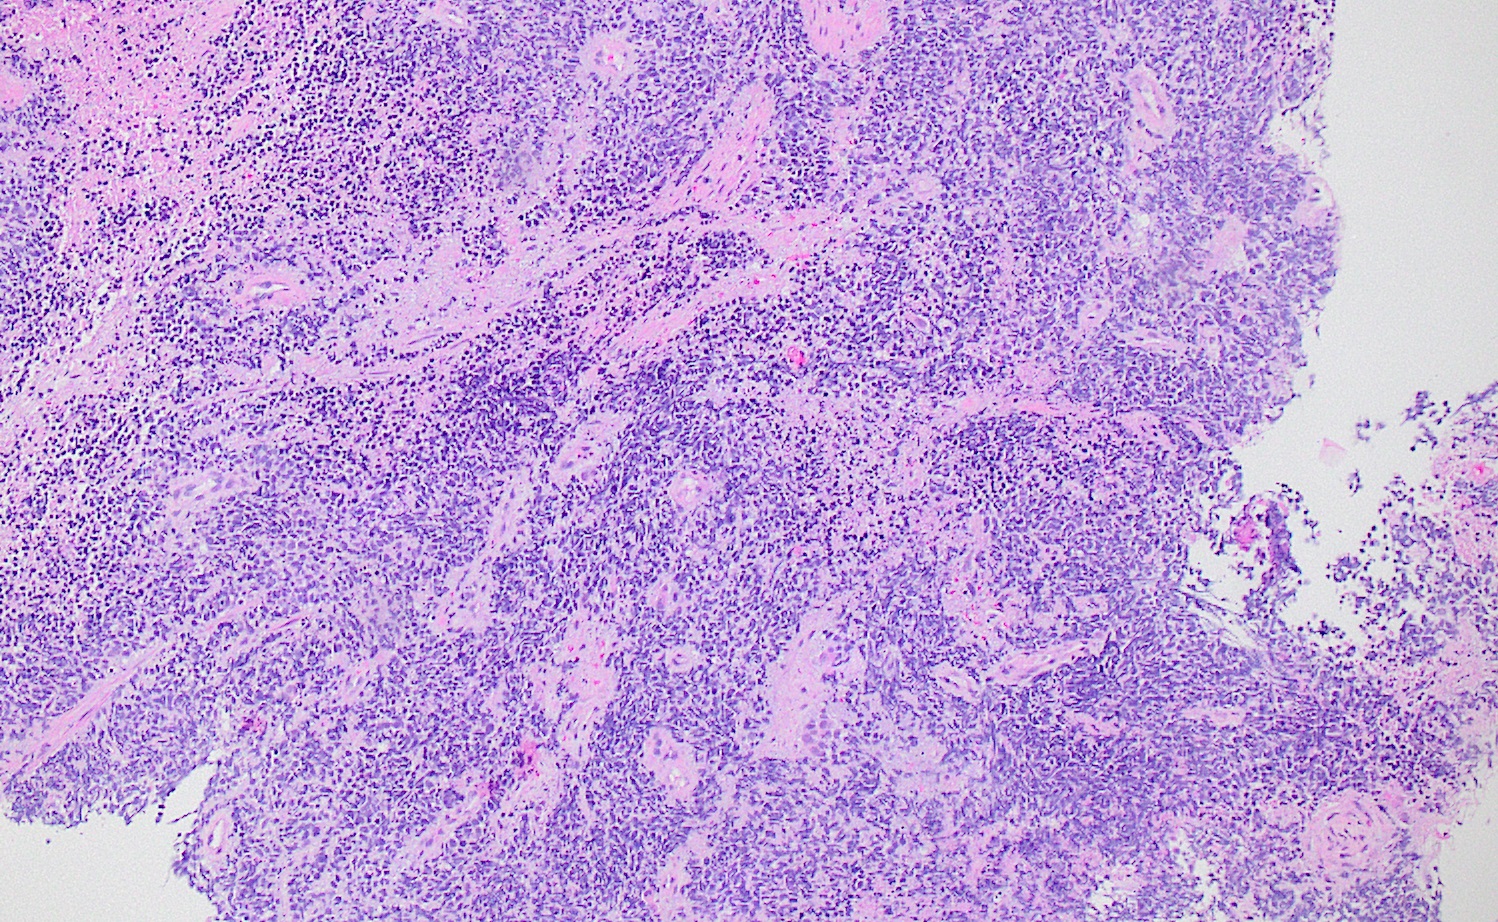

A 75 year old man with a 100 pack year smoking history presents with hemoptysis and is found to have a hilar mass and lymphadenopathy. Biopsy of one of the lymph nodes reveals the proliferation seen in the above images. Mitotic activity is approximately 35 mitoses per 2 mm2 and necrosis is present. Immunophenotyping is attempted; however, the block was inadvertently exhausted and stains are not available. What is the best diagnosis that can be rendered?

- Small cell carcinoma

Board review style answer #3

E. Small cell carcinoma. Small cell carcinoma remains a morphologic diagnosis and does not require immunophenotyping for confirmation. The clinical history and description of the malignant cells are consistent with a diagnosis of small cell carcinoma. Immunophenotyping, including the use of Ki67, is most useful in cases with more ambiguous morphologic features or in crushed biopsies where morphologic features are obscured.